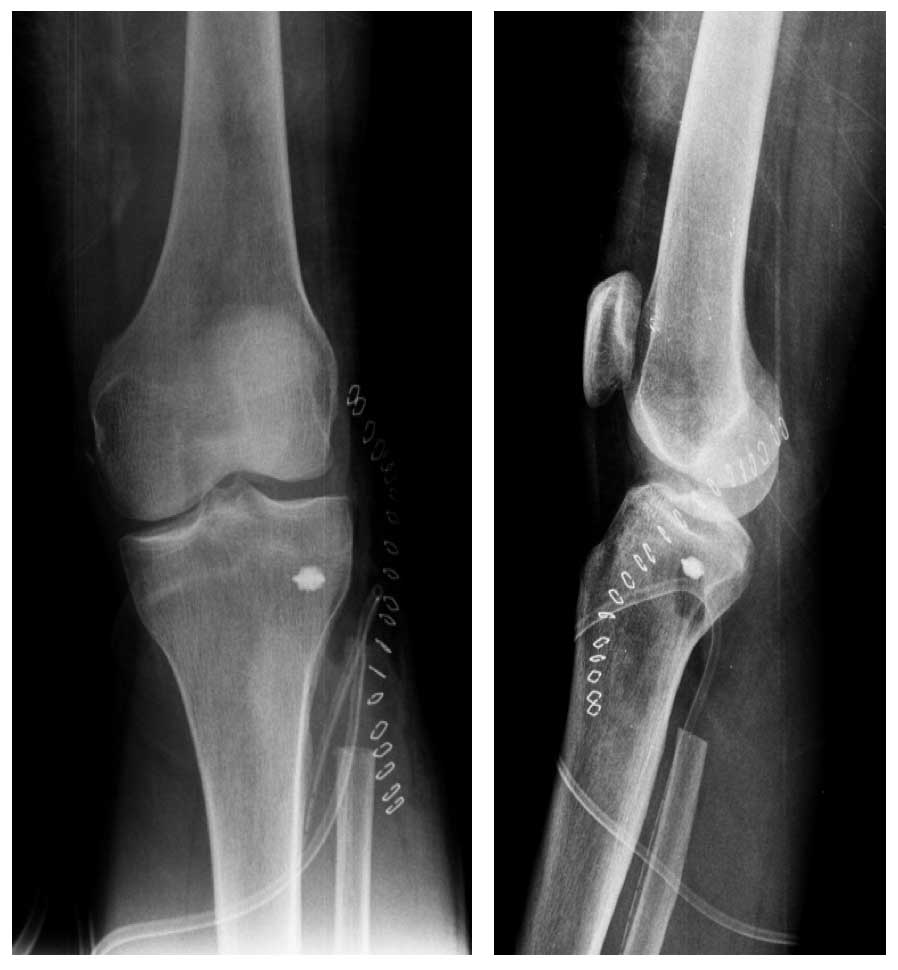

Ameliyat Sonrası: Röntgende proksimal fibula rezeksiyonu ve anchor yerleşimi görülmekte.